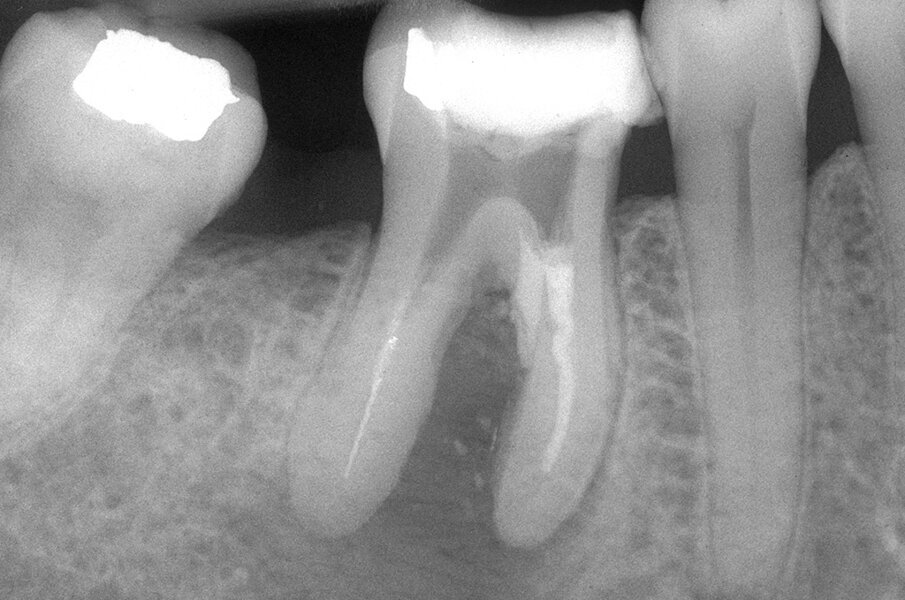

Queste perforazioni possono avvenire nel corso della strumentazione di canali curvi, per l’esecuzione del cosiddetto “trasporto esterno” del forame apicale. Una volta eseguita la perforazione, se l’operatore riesce a ritrovare e preparare il canale originale (con l’utilizzo di strumenti sottili e precurvati, molta irrigazione e soprattutto molta pazienza), il danno provocato dalla perforazione sarà minimo in quanto, soprattutto se la perforazione è piccola, si comporterà come un piccolo canale laterale che sarà facilmente otturato. Se invece il canale originale è rimasto intasato dai detriti di fango dentinale e gli strumenti ogni volta ripercorrono il cammino della perforazione, in tale caso il canale deve essere otturato con le metodiche tradizionali e successivamente l’apice contenente la porzione non trattata del canale radicolare deve essere rimosso per via chirurgica, soprattutto se stiamo trattando un dente necrotico o se siamo di fronte ad un ritrattamento (Figg. 1a-1e).

Le perforazioni del terzo medio avvengono nella maggior parte dei casi durante la preparazione della cavità d’accesso o, più spesso, durante le fasi di detersione e sagomatura o infine durante la preparazione dello spazio per un perno con l’utilizzo di frese tipo Largo, Peeso, Gates Glidden o simili (Figg. 2a-2f).